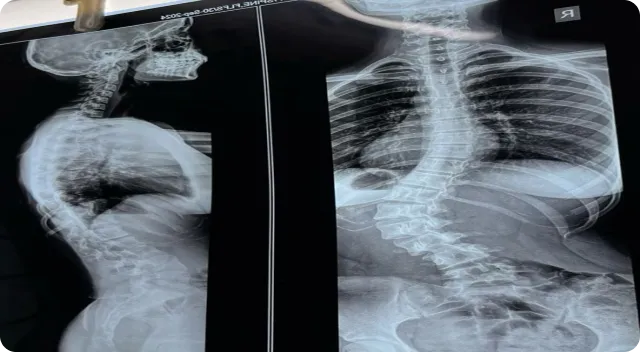

Spinal cord injury (SCI) is a neurological condition that occurs when damage to the spinal cord influences communication between the brain and different parts of the body. The functional impact varies depending on the injury level, severity, and individual health factors, often affecting mobility, sensation, or coordination. Long-term management commonly includes structured rehabilitation programs, physiotherapy, and assistive support strategies.

In regenerative medicine, umbilical cord–derived mesenchymal stem cells (MSCs), frequently combined with exosomes therapy, are increasingly studied as supportive biological approaches aimed at assisting cellular communication pathways, inflammation balance, and neurological signaling under professional medical supervision. In Turkey, regenerative therapy for spinal cord support is performed using GMP-certified laboratory-processed biologic materials and individualized treatment planning based on medical imaging and neurological evaluation. These therapies are described as complementary supportive options, not cures or guaranteed outcomes.

A spinal cord injury can result from trauma, compression, or medical conditions affecting spinal tissues. Depending on the injury location, individuals may experience variations in movement, muscle strength, sensory perception, or autonomic function. Because every injury profile is unique, multidisciplinary care involving neurologists, rehabilitation specialists, and physiotherapists is typically recommended to support long-term functional goals.